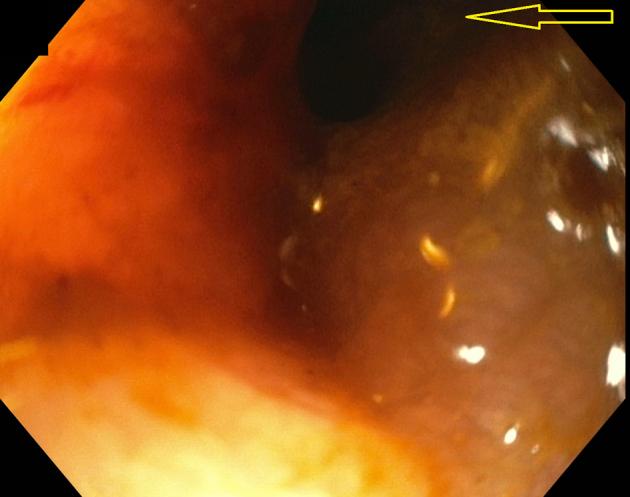

In this video case series, 3 cases of CVF patients treated endoscopically are presented to demonstrate the use of the currently available tools and techniques. The strategy used for the closure of the 3 CVFs was dependent on the size and etiology of the fistulas.

These cases demonstrate the use of the cap to perform vaginal endoscopy; the use of the over-the-scope clips, covered stents, and endoscopic suturing; and how they can facilitate the closure of fistulas in patients who are poor surgical candidates.